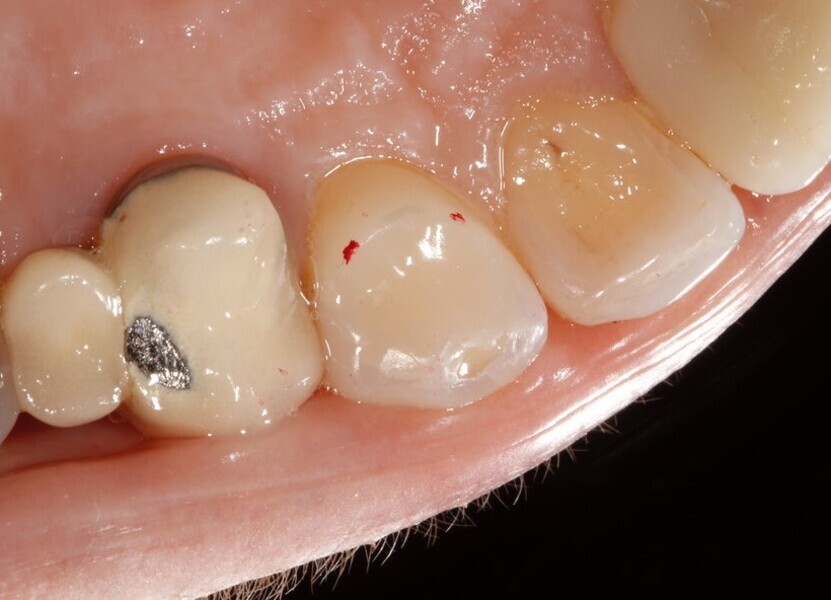

Discoloured maxillary central incisors. (All images: Tif Qureshi)

A 48-year-old female patient came to see me in 2004. The patient initially presented because she was unhappy with her two discoloured maxillary central incisors (Fig. 1). She also had chipping and wear of the mandibular teeth and broken posterior bridgework. Her “bite” also felt uncomfortable (Fig. 2).

Fig. 1: 2004—discoloured maxillary central incisors.